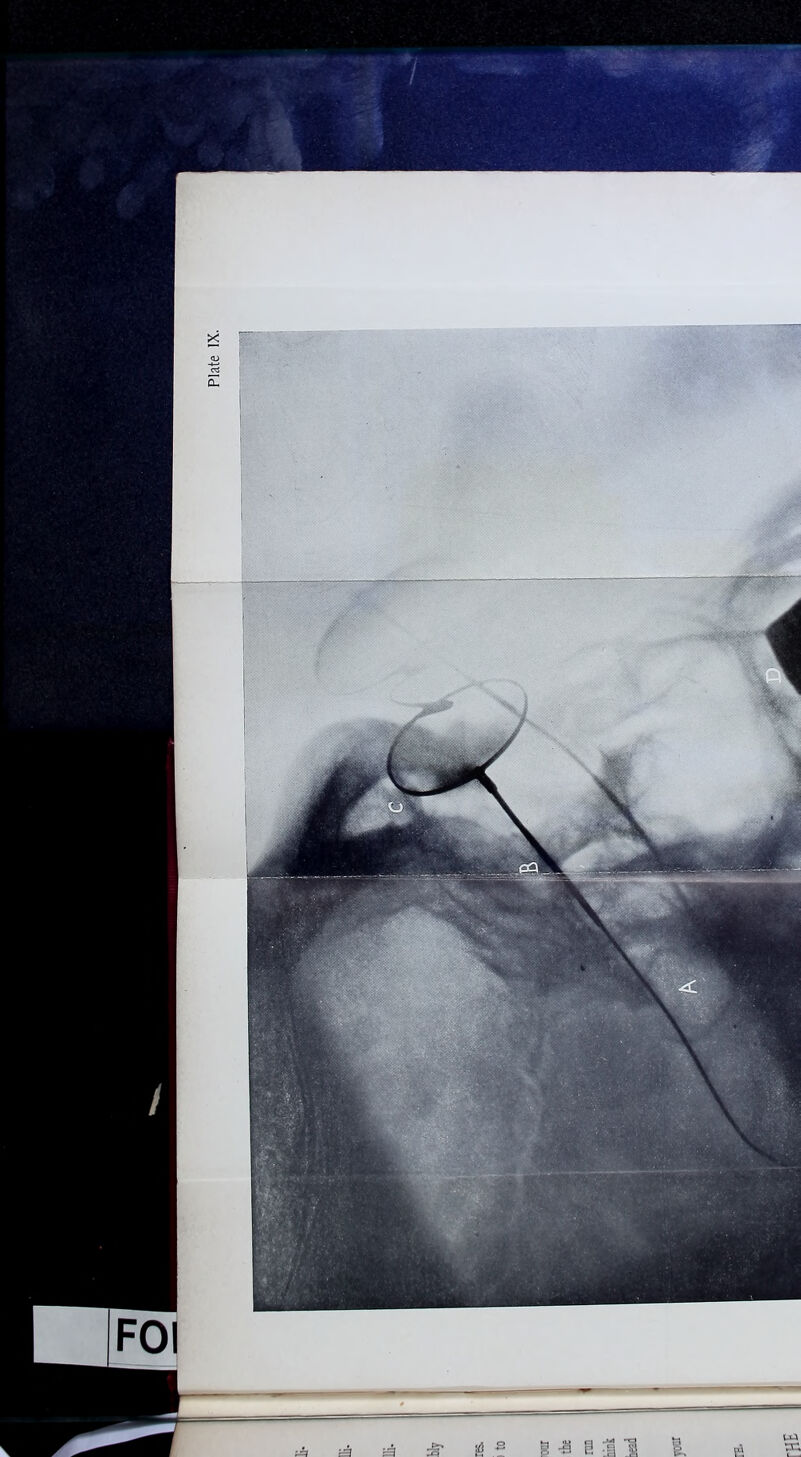

Acromegaly : a personal experience / by Leonard Portal Mark.

170/192 page 153